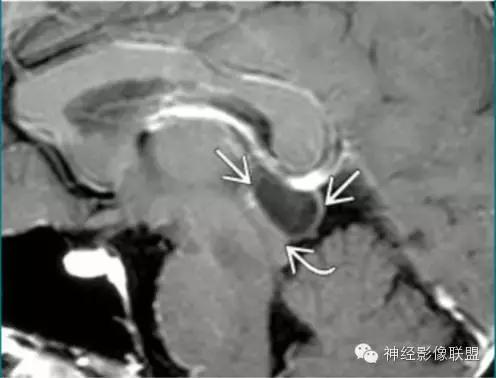

Rathke裂囊肿